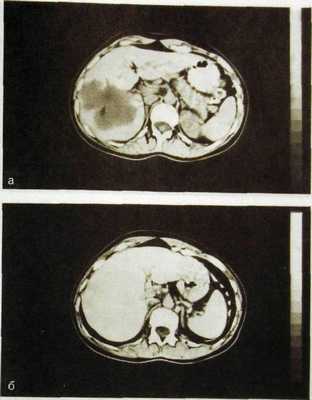

Рис. Ш.140. Компьютерные томограммы печени с усилением. Кавернозная ге-мангиома печени.

а — до внутривенного введения контрастного вещества; б — после его введения: изображение гемангиомы почти исчезло (контрастное вещество заполнило сосудистые пространства опухоли).